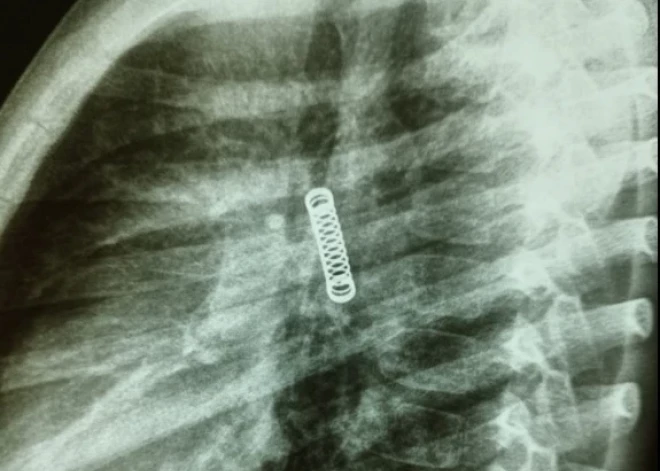

Vecāki atveda zēnu uz slimnīcu, jo kopš pērnā gada decembra viņš pastāvīgi klepojis. Pārsteigtie ārsti kreisās plaušas rentgenuzņēmumā ieraudzījuši atsperi. 8. martā veiktajā operācijā atsperi izdevās izņemt.

Ķirurgs Karloss Morinigo sacīja, ka operāciju apgrūtināja atsperes ilgstošā atrašanās organismā, un šo triju mēnešu laikā bērna elpceļi ir nopietni bojāti. Tomēr ārsti cer, ka laika gaitā plaušu audi reģenerēsies un atsāks maksimāli efektīvu darbu.